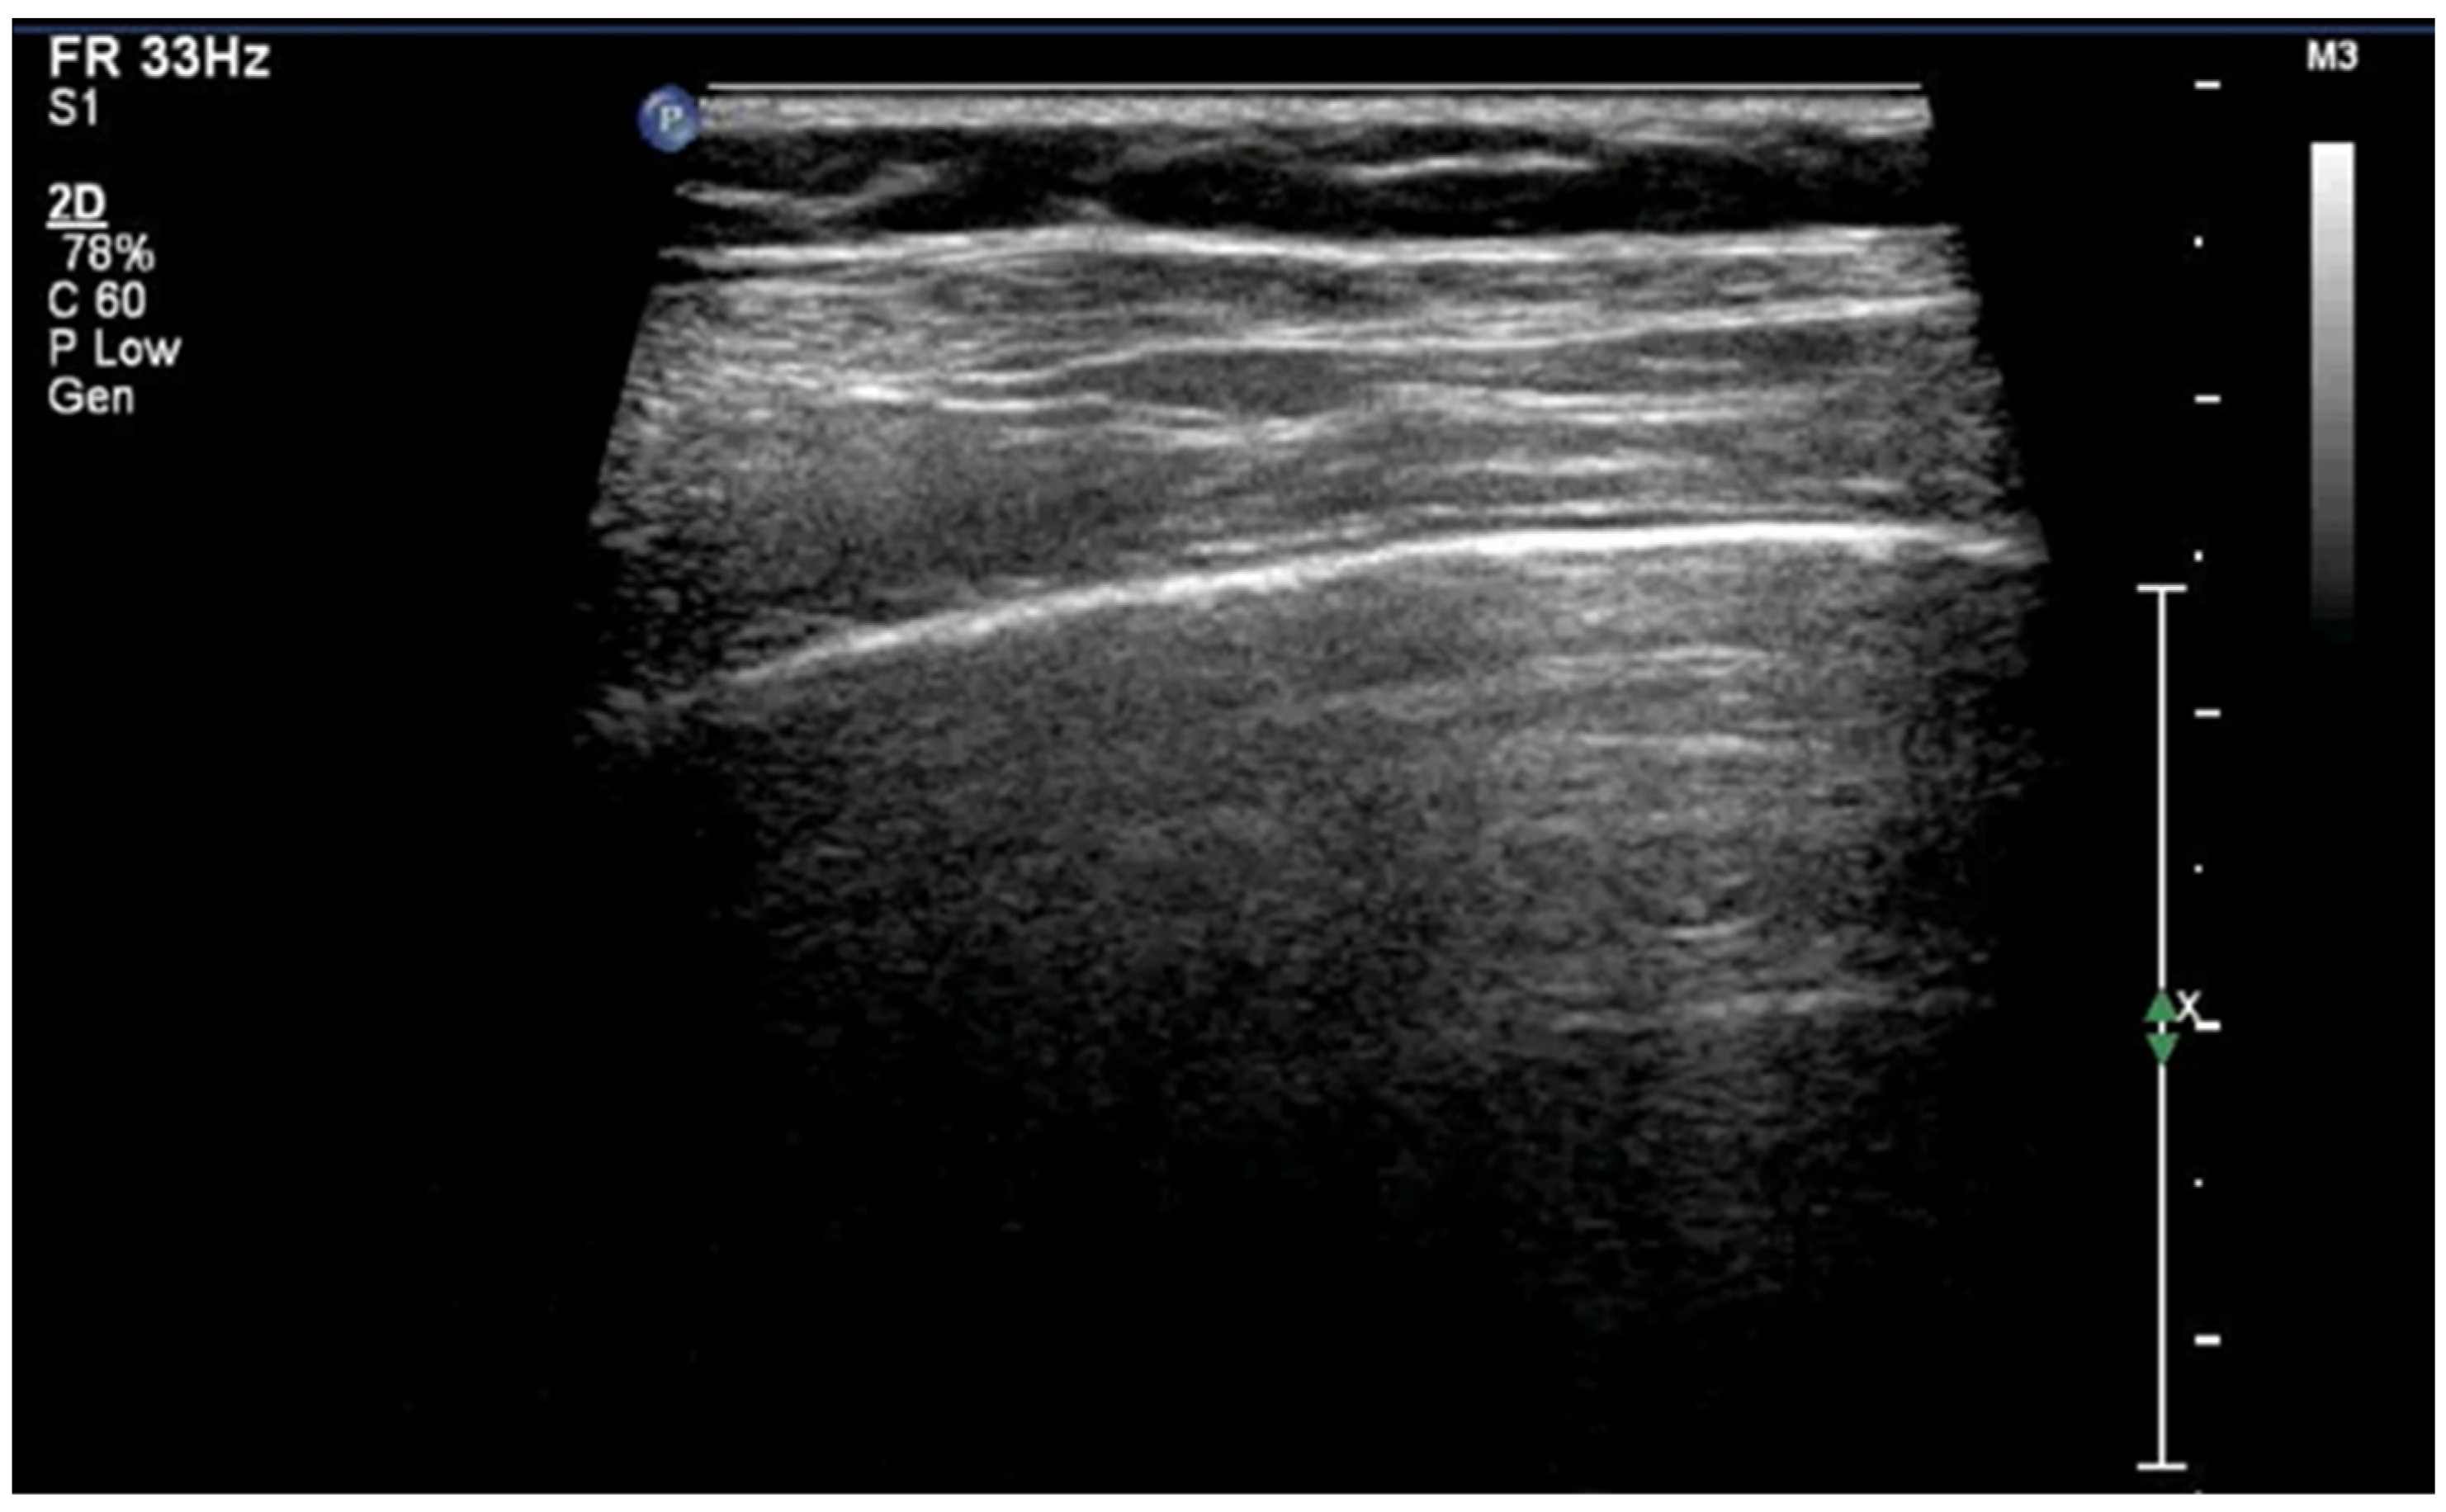

3.1.3. Pleural Line